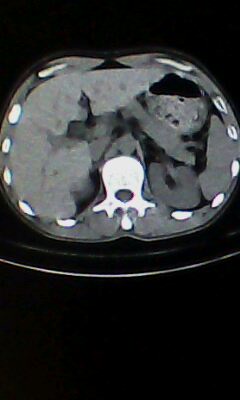

胰尾部占位?

未见明显异常。“胰尾占位”为肠管

口服造影剂是必须的

弥漫性肺气肿 但内胆管轻度扩张